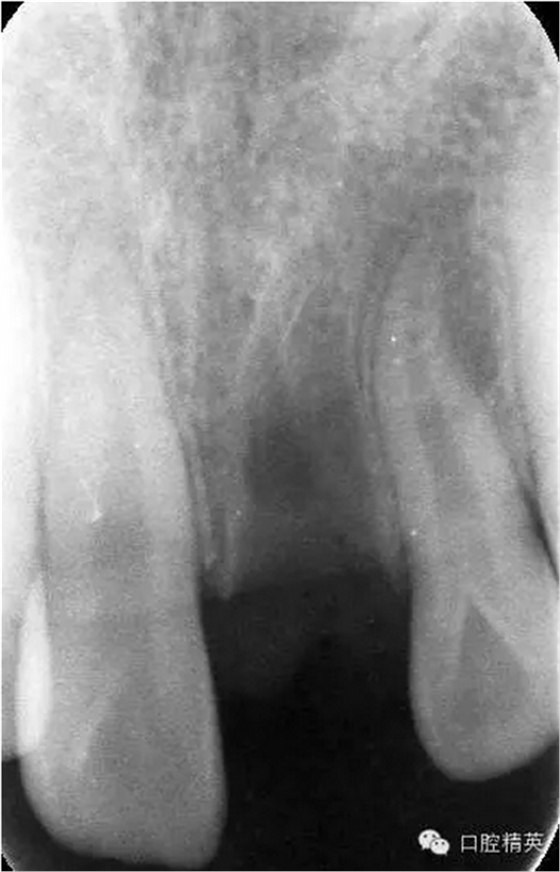

x線檢查:21牙槽窩空虛,窩內(nèi)未見其他遺留物。

圖3.患者21根尖片,牙槽窩空虛,無變形。